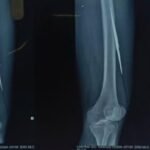

सुकमा में घरेलू विवाद के दौरान एक व्यक्ति अपने ही पुत्र द्वारा किए गए हमले में गंभीर रूप से घायल हो गया था। घटना में पीड़ित की जांघ में एक तीर धंस गया था, जबकि दूसरा तीर कलाई के पास घुसकर हाथ की महत्वपूर्ण नस (नर्व) को दबा रहा था। स्थिति अत्यंत संवेदनशील थी। समय रहते उपचार न मिलने की स्थिति में हाथ की स्थायी क्षति हो सकती थी और पीड़ित की जान को भी खतरा हो सकता था। घायल को तत्काल जगदलपुर डिमरापाल चिकित्सालय लाया गया, जहां रात्रि लगभग 2 बजे आर्थोपेडिक्स विभाग की टीम ने तत्परता से उपचार प्रारंभ किया। सहायक प्राध्यापक, आर्थोपेडिक्स विभाग डॉ. आदित्य कौशिक ने विभागाध्यक्ष डॉ. सुनीत पाल के मार्गदर्शन में जटिल शल्य प्रक्रिया को सफलतापूर्वक अंजाम दिया। चिकित्सकीय जांच में पाया गया कि यद्यपि रोगी हेमोडायनामिक रूप से अस्थिर नहीं था, फिर भी कलाई में धंसा तीर नस पर दबाव बना रहा था, जिससे स्थायी नर्व डैमेज का गंभीर खतरा उत्पन्न हो गया था। टीम द्वारा अत्यंत सावधानी और विशेषज्ञता के साथ दोनों तीरों को सुरक्षित रूप से निकाला गया। विशेष रूप से कलाई क्षेत्र में की गई सटीक प्रक्रिया के माध्यम से हाथ की नस को होने वाली संभावित क्षति को समय रहते रोक लिया गया। इस जटिल हस्तक्षेप में एनेस्थीसिया विशेषज्ञ डॉ. गुलाब सिंह काशी ने कुशलता से उपयुक्त क्षेत्रीय एनेस्थीसिया प्रदान किया, जिससे पूरी प्रक्रिया सुरक्षित और सुचारु रूप से सम्पन्न हो सकी। चिकित्सकों के अनुसार, ऐसी चोटें अत्यंत घातक सिद्ध हो सकती हैं, विशेषकर जब वे नसों के समीप हों। मध्य रात्रि में त्वरित निर्णय, अनुभवी चिकित्सकीय हाथों और समन्वित टीमवर्क के कारण यह जीवन-रक्षक उपचार संभव हो पाया। वर्तमान में रोगी की स्थिति स्थिर है और हाथ की कार्यक्षमता सुरक्षित रहने की उम्मीद जताई गई है। डॉक्टरों के टीम वर्क, अस्पताल अधीक्षक डॉ. अनुरूप साहू के कुशल नेतृत्व, समय पर चिकित्सकीय हस्तक्षेप के महत्व को और हॉस्पीटल में उपलब्ध विशेषज्ञ सेवाओं और चिकित्सकों की प्रतिबद्धता का प्रमाण प्रस्तुत करती है। डिमरापाल मेडिकल कॉलेज के अधीक्षक डॉ. अनुरूप साहू के कुशल निर्देशन में डाक्टरों की टीम बेहतर व्यवस्था के साथ मरीजों की देखरेख में जुटी है। हॉस्पीटल में साय सरकार के सुशासन की झलक साफ नजर आने लगी है।